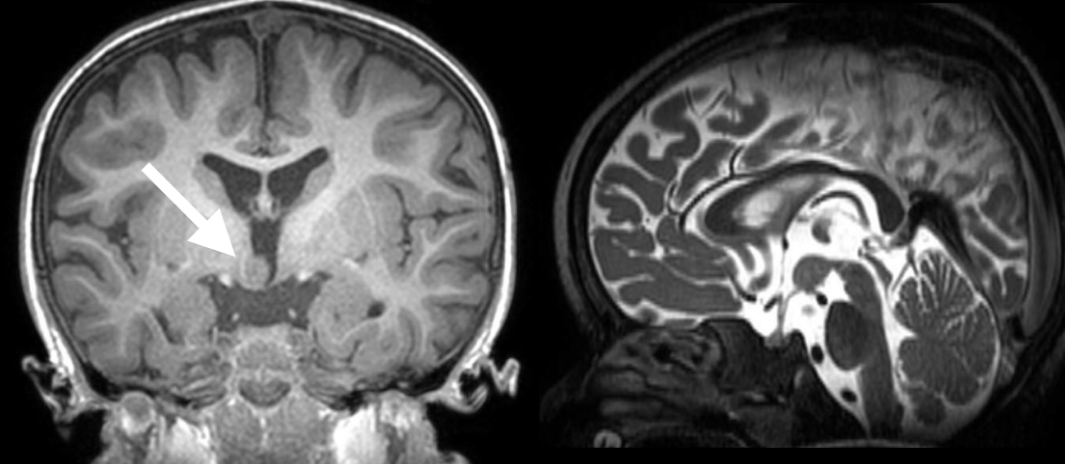

激光间质热疗(LITT)过程。(A)描绘左侧海马硬化的轴向T2加权和矢状面衰减倒置恢复(FLAIR)磁共振成像(MRI)切片。(B)通过枕骨入路沿海马长轴插入的激光探针。(C)激光消融后获得的早期T1对比增强MRI显示病变的大小。